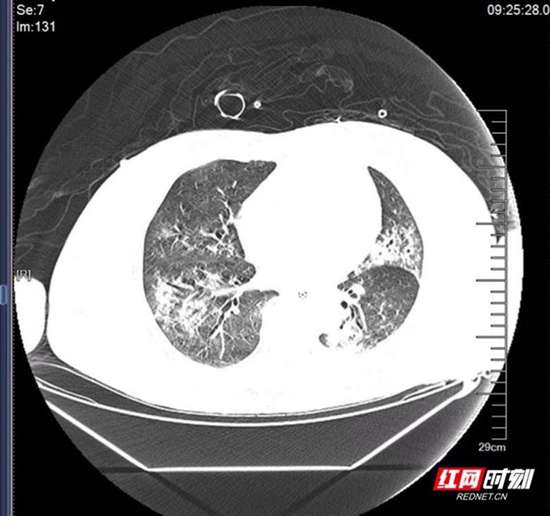

治疗后。

在医护人员精心照护下,患者生命体征逐渐平稳。经过一周持续努力,其“白肺”情况明显好转,最终成功撤除ECMO及呼吸机。为进一步促进康复,医疗团队将重点转向后续康复治疗,助力患者早日转出重症病房。